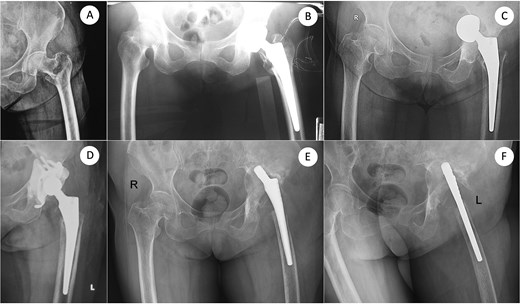

A 73-year-old woman presented with severe bone loss of the left proximal femur and extensive acetabular deficiency with pelvic discontinuity (Fig. 1). Initial treatment in 2017 for a displaced femoral neck fracture was bipolar hemiarthroplasty (Fig. 2A and B). After a new injury in 2019, an acetabular fracture with intrapelvic migration of the bipolar head occurred (Fig. 2C), leading to conversion to total hip arthroplasty with a revision acetabular component supported by a cup–cage (“trap”) construct (Fig. 2D). In 2023, PJI developed with loosening of both components; the acetabular component was explanted and a central pedicled vastus lateralis flap transposed to manage dead space (Fig. 2E and F). In May 2024, the femoral component was removed (Fig. 3A). CT confirmed mixed cavitary–segmental acetabular defects and marked metaphyseal loss of the proximal femur (Fig. 3B). After normalization of inflammatory markers and soft-tissue healing, salvage re-revision THA was performed. Acetabular reconstruction used a 52-mm porous shell–cage; two 45-mm tongues engaged host ilium and ischium, and cavitary defects were filled with antibiotic-loaded polymethylmethacrylate. Fixation comprised three intra-shell screws, four rim screws, and two tongue screws (Fig. 3C). On the femoral side, 2 cm of compromised proximal femur was resected to bleeding bone; the canal was reamed to 15 mm for circumferential endosteal contact. A modular tapered, fluted stem (14 × 260 mm) achieved distal fixation, supplemented by two distal interlocking screws; prophylactic cerclage mitigated iatrogenic fracture risk (Fig. 3C). Postoperatively, weight bearing advanced as tolerated. Serial AP pelvis radiographs showed a stable cup–cage without migration or progressive radiolucency and a well-seated stem without subsidence. At 10 months there were no complications, no infection or dislocation, and the patient ambulated with a cane; radiographs remained stable (Fig. 2D).

From femoral neck fracture and bipolar hemiarthroplasty to acetabular perforation, conversion THA, and acetabular component removal. (A) Anteroposterior (AP) pelvis radiograph demonstrating a displaced femoral neck fracture. (B) Immediate postoperative AP view after bipolar hemiarthroplasty using a standard femoral stem. (C) Subsequent acetabular perforation with intrapelvic migration of the bipolar head. (D) Conversion to total hip arthroplasty with an acetabular component supported by a cup–cage construct. (E, F) Same sitting: AP and cross-table lateral views obtained at the time of acetabular component explantation, delineating extensive acetabular bone loss. AP, anteroposterior.